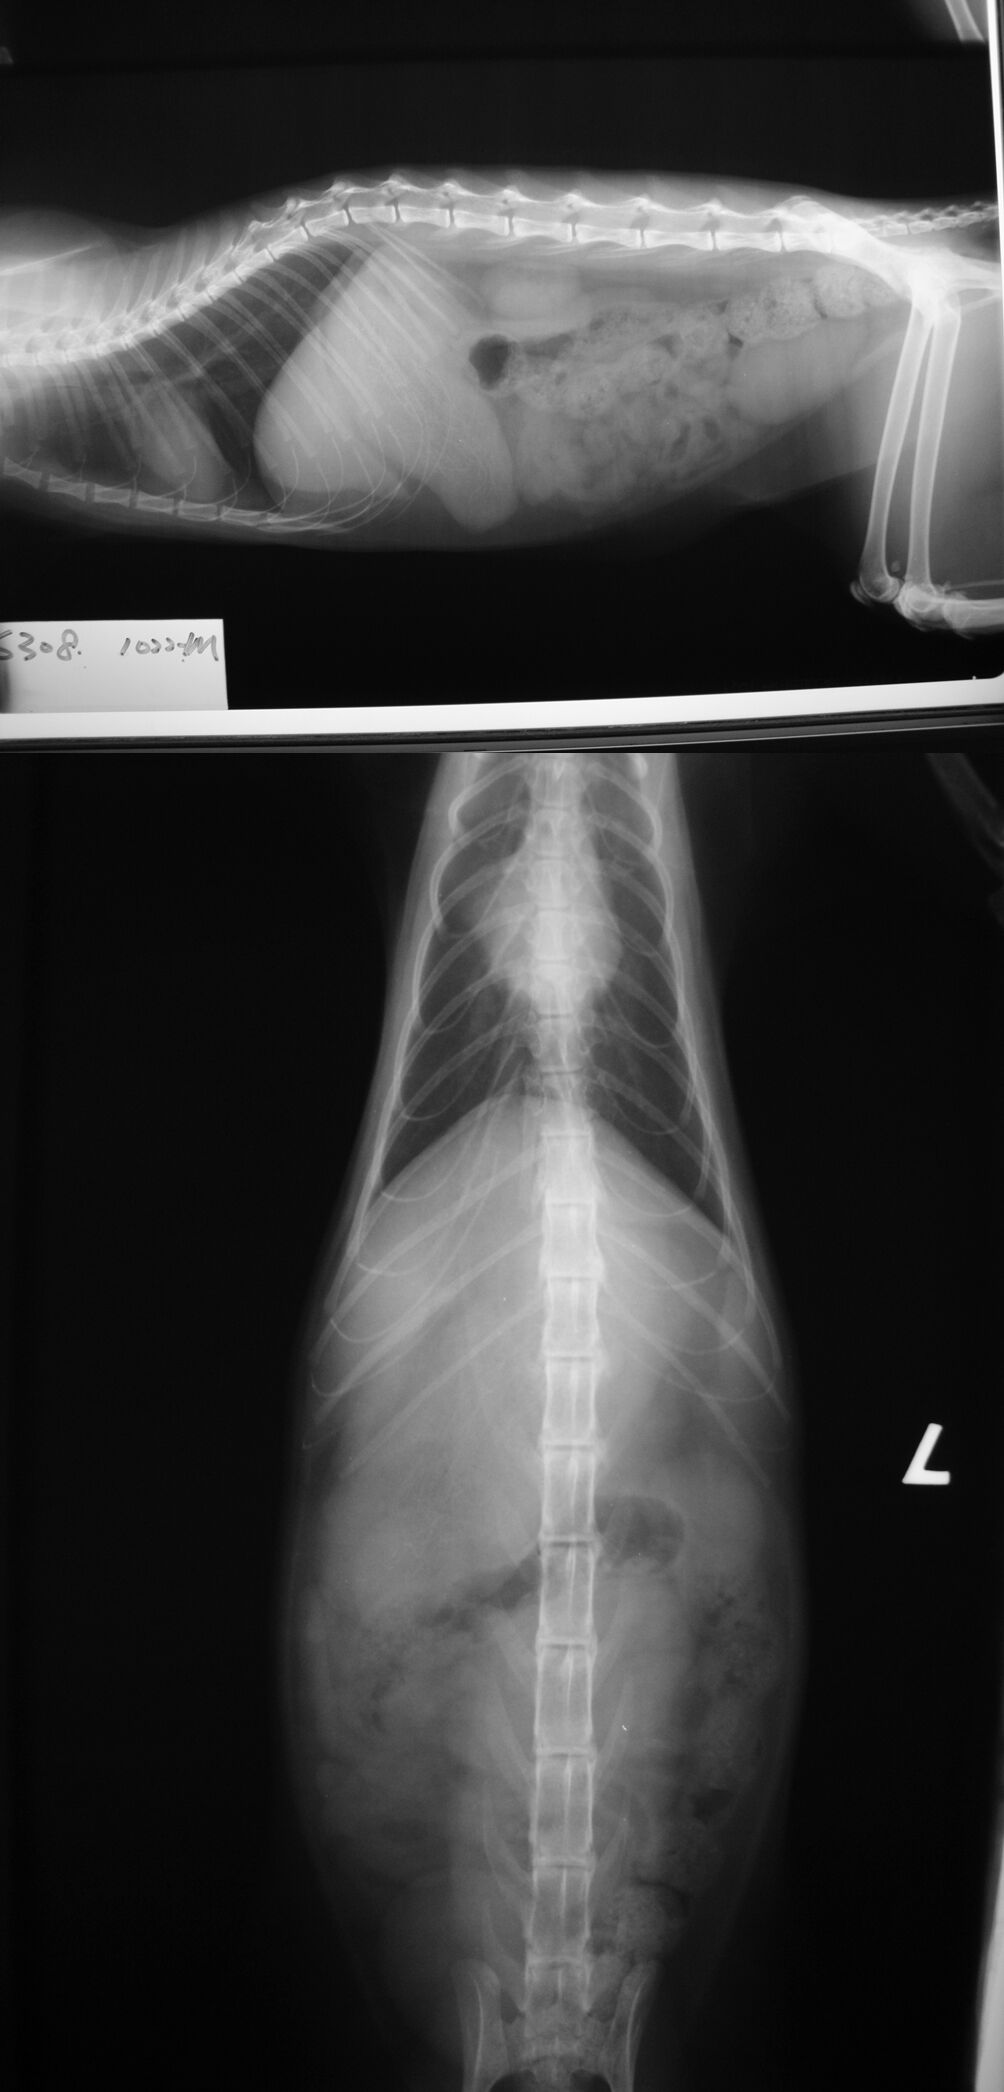

主題: 愛河邊消瘦吐血的貓咪 申請者姓名: 劉素鳳 花色: 申請日期: 2013-11-12 11:50:38 申請者部落格: 申請者臉書網址: 所在縣市/合作醫院: 高雄市/樂生動物醫院 治療費用: 13800元 需求人數: 15人 已結案 (2014-01-10 17:53:52) 報名人員: grace0710(已付款)、JIN、Yunnami Liu(已付款)、Yunnami Liu(已付款)、林羿如(已付款)、WeiLin Chen x2(已付款)、su.6rmp4fu;6、su.6rmp4fu;6、牛俊強(已付款)、orange(已付款)、Emily Chou(已付款)、ERic YU(已付款)、orange(已付款)、曾淑湘(已付款)、Chin Fang Lai(已付款)、sharonhuang9(已付款)、迷你古柏(已付款)、 候補人員: 動物病情說明: 這隻是在愛河旁固定餵食的浪貓之一,已有很長時間看牠在吐,由於餵食時間都是在於晚上而看不清楚牠所吐的東西,而今天提早經過餵食看牠吐的是血,嚇死我了,難怪看牠一天比一天消瘦,趕緊誘補進籠送合作的醫院醫治! 就醫後醫生檢查發現貓的胃裡有異物須開刀, 開刀取出了好大一團黑黑的塑膠線條的東西, 懷疑是貓咪愛玩會是亂吃下肚的東西, 還好手術一切順利, 貓已經健康出院了.

目前安置她想要送養看看, 幫她找一個家.